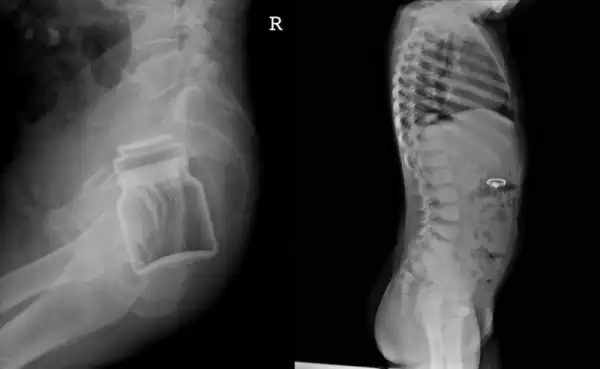

Вся суть медицины в одном фото